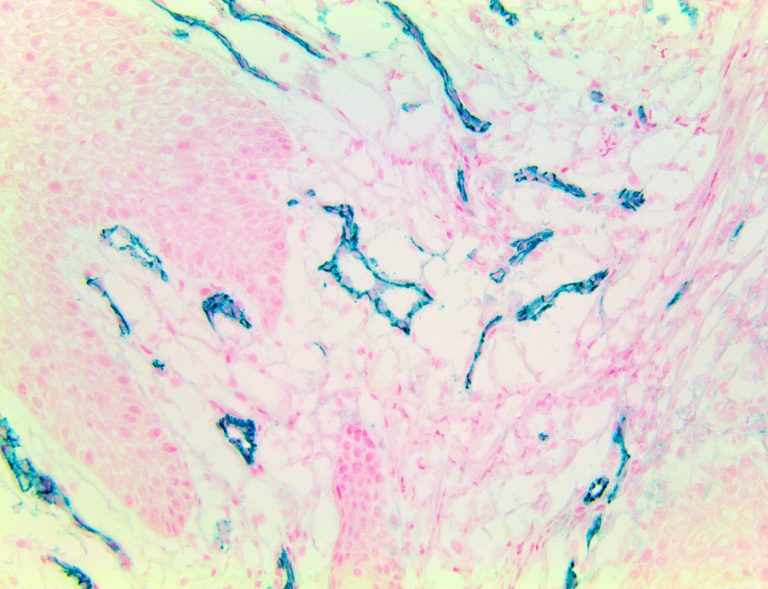

| TintoFast CD31 is also called PECAM-1 for platelet endothelial cell-adhesion molecule. It plays a key role in removing aged neutrophils from the body. CD-31 is normally found on stem cells, endothelial cells, platelets, macrophages and Kupffer cells, granulocytes, T/NK cells, lymphocytes, megakaryocytes, fibroblasts, osteoclasts and neutrophils. CD31 is also expressed in certain tumors, including Epithelioid Hemangioendothelioma, Epithelioid Sarcoma like Hemangioendothelioma, other vascular tumors, Histiocytic malignancies, and Plasmacytomas. It is rarely found in some sarcomas and carcinomas. CD31 and macrophages play a key role in tissue regeneration. TintoFast CD31 is widely used to identify the vascular origin of neoplasms, as it is a highly specific and sensitive marker for vascular endothelial cells. |

| Localization | Cytoplasmic, Membranous | Control | Tonsil, Placenta, Appendix, Spleen, Kidney | |